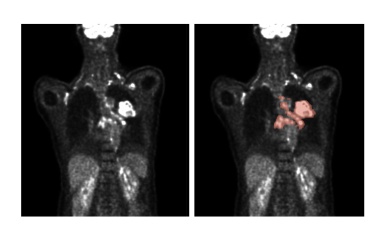

Künstliche Intelligenz kann die Auswertung von medizinischen Bilddaten verbessern. So können auf Deep Learning basierende Algorithmen die Lage und Größe von Tumoren feststellen.